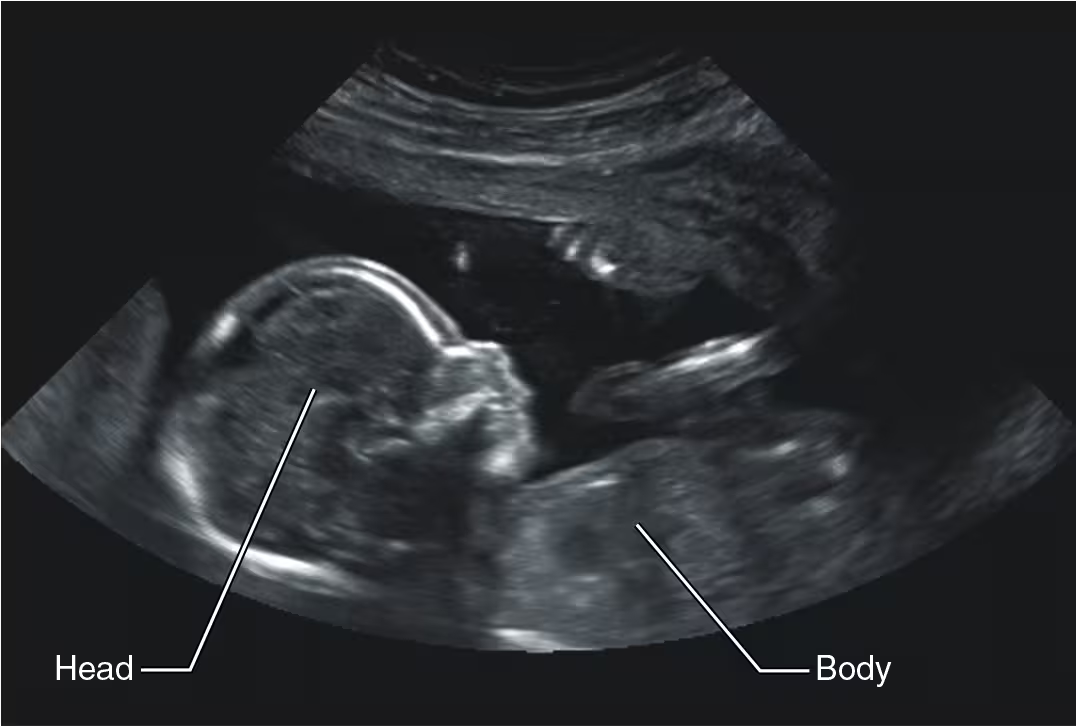

How does ultrasound imaging work?

it uses high-frequency sound waves that reflect off of the body’s tissues

What is ultrasound imaging used for?

monitoring a fetus during pregnancy

diagnosing abdominal or pelvic disorders

detecting atherosclerosis and heart valve disorders

What is the drawback of ultrasound imaging?

images tend to be lower resolution